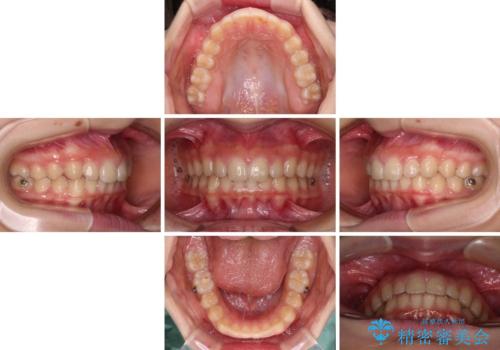

海外で始めたインビザライン 転医手続きにより治療を継続

- ヨーロッパにてインビザライン矯正を始めたものの、日本に転居することになり、治療の継続を希望して来院された患者様です。

治療計画に無理がなく、現地担当医と速やかに連絡が取れるとのことで、インビザライン社での転医手続きを行い、継続して治療を行うこととしました。

舌の突出癖により、上下前歯が非接触となっていたため、トレーニングを徹底的に指導し、安定した咬み合わせにより終了させることができました。